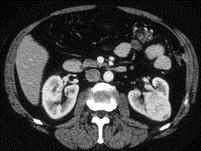

问题 女,47岁,左侧腰部隐痛不适2 月余,请结合下列图片作出诊断 ( )

选项 A、左肾炎性包块 B、左肾感染性囊肿 C、左肾血管平滑肌脂肪瘤 D、左肾出血性囊肿 E、左肾癌

答案 E